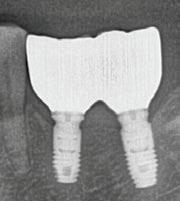

Depuis 1990, Implant Québec agit comme centre de référence pour la gestion des complications en implantologie, tant chirurgicales que prothétiques.

Ce qui nous distingue particulièrement, c’est notre savoir-faire en gestion des complications prothétiques et chirurgicales, un domaine souvent complexe et exigeant sur le plan clinique.

Ce service est offert grâce à une équipe expérimentée capable d’intervenir dans les situations les plus délicates et à une vaste expertise acquise depuis plus de 30 ans dans le domaine.

Nous accompagnons les professionnels et leurs patients dans divers contextes, notamment :

Péri-implantite

Restauration problématique

Reprise de cas complexes